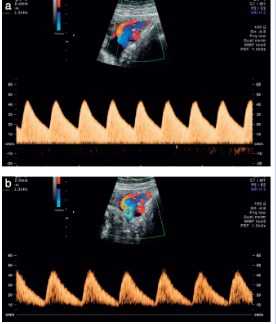

Основная ветвь маточной артерии легко находится с помощью цветного изображения в режиме реального времени. Измерения скорости кровотока обычно выполняются трансабдоминальным или трансвагинальным датчиком. Измерения следует проводить в правой и левой маточной артерии (Рис.1).

Рис.1. Форма волны кровотока в маточной артерии, полученная трансабдоминальным датчиком в первом триместре беременности.

Оценка маточной артерии в первом триместре беременности (Рис.1)

- Методика трансабдоминального сканирования

- Трансабдоминальный трансдьюсер размещается таким образом, чтобы визуализировать среднесагиттальный срез матки и цервикальный канал. Обследование проводится с пустым мочевым пузырем.

- Трансдьюсер перемещаем латерально, пока не визуализируем парацервикальное сосудистое сплетение.

- Включаем цветной допплер и обнаруживаем маточные артерии.

- Измерение проводится в отрезке сосуда перед разветвлением маточной артерии на аркуатные артерии.

- То же повторяем с противоположной стороны.

Методика проведения цветной допплерографии артерии пуповины

Существует значительная разница в показателях допплера, измеренных на эмбриональной части пуповины, свободной части и плацентарной части пуповины. Для простоты и последовательности, измерения следует проводить в свободной части пуповины (Рис.3).

Рис.3. Допустимые (а) и недопустимые (b) формы кривой при проведении допплерографии в пупочной артерии. На сонограмме b графические изображения кривой слишком малы, а скорость слишком медленная.